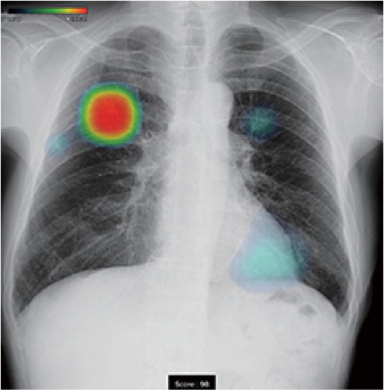

先のCXR-AID解析した100件のうち、Low評価(スコア15未満)が67人。3分の2が私の読影およびCXR-AIDの解析とも、まったく所見がない患者さんでした。CXR-AID解析による評価の詳細は、スコア0~20が10件、同20~40が14件、同40~60が2件、同60~80が4件、同80~98が3件で、ヒートマップの赤色表示であるスコア50以上が8件という状況でした。この評価と読影の結果、CT検査を実施したのは、それぞれスコア0~20で1件、同20~40で1件、同40~60で1件、同60~80で1件、同80以上で2件の計6件です。

例えば、69歳男性の症例(図1)では、私の読影で3か所に陰影があり、そのうち2か所は立位側面画像でも明らかに陰影を認めることができました。一方、CXR-AIDの解析では、1か所を赤色で評価し、3か所を青色で評価していました。

この患者をCT撮影したところ、CXR-AIDの解析と同じく4か所に病変を認めることができました。これらの結果を踏まえれば、CXR-AIDは私が胸部X線画像で見過ごした粒状影の淡い陰影も検出した一方、赤色と青色で評価が分かれた2か所については、両か所とも赤色で評価してもいいのではないかと思われ、スコアリングの数値に頼り過ぎないようにしなければならないと思いました。この症例では、もし4か所の陰影をすべて青色で評価していれば、CT撮影を実施せず、見逃されたかもしれません。そういう意味では、CXR-AIDの全体的な評価精度は高いと思います。

胸部立位正面画像

CXR-AID解析画像